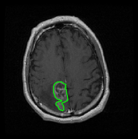

We argue that the sub-optimal paradigm of processing different abstractions within a single CNN pipeline can be remedied through the effective processing of information in a structured manner. Consequently, we devise strategies for disentangling the edge and texture information within a single training pipeline. Figure 2 illustrates how our proposed module, dubbed EG-CNN, can be paired with any existing CNN encoder-decoder to improve segmentation quality near intensity edges. We have applied our EG-CNN to the tasks of brain and liver tumor segmentation in medical images (Figure 3).

(1) Brain MR (2) Liver MR (3) Liver CT (4) Lung CT

We first introduce a method for connecting the output of a CNN to an ACM, yielding a model for the precise delineation of lesions, to which we refer as Deep Active Lesion Segmentation (DALS) (Figure 4). We then go further to introduce a truly unified framework (Figure 5) that bridges the gap between ACMs and CNNs by leveraging a novel, automatically differentiable level-set ACM with trainable parameters that allows for back-propagation of gradients and can be end-to-end trained along with a backbone CNN from scratch, without any CNN pre-training. The ACM is initialized directly by the CNN and utilizes an energy functional that is locally-tunable by the backbone CNN, through 2D feature maps. Thus, our work overcomes the big hurdle of fully automating the powerful ACM approach to image segmentation. We have applied our proposed framework to the task of building segmentation in aerial images (Figure 6).

Edge-Aware 2D Image Segmentation Networks

[49; 48]: Fully convolutional neural networks (CNNs) have proven to be effective at representing and classifying textural information, thus transforming image intensity into output class masks that achieve semantic image segmentation. In medical image analysis, however, expert manual segmentation often relies on the boundaries of anatomical structures of interest. We propose 2D edge-aware CNNs for medical image segmentation. Our networks are designed to account for organ boundary information, both by providing a special network edge branch and edge-aware loss terms, and they are trainable end-to-end. We validate their effectiveness on the task of brain tumor segmentation using the BraTS 2018 dataset. Our experiments reveal that our approach yields more accurate segmentation results, which makes it promising for more extensive application to medical image segmentation. -

Deep Active Lesion Segmentation

[45]: Lesion segmentation is an important problem in computer-assisted diagnosis that remains challenging due to the prevalence of low contrast, irregular boundaries that are unamenable to shape priors. We introduce Deep Active Lesion Segmentation (DALS), a fully automated segmentation framework that leverages the powerful nonlinear feature extraction abilities of FCNs and the precise boundary delineation abilities of ACMs. Our DALS framework benefits from an improved level-set ACM formulation with a per-pixel-parameterized energy functional and a novel multiscale encoder-decoder CNN that learns an initialization probability map along with parameter maps for the ACM. We evaluate our lesion segmentation model on a new Multiorgan Lesion Segmentation (MLS) dataset that contains images of various organs, including brain, liver, and lung, across different imaging modalities—MR and CT. Our results demonstrate favorable performance compared to competing methods, especially for small training datasets. -